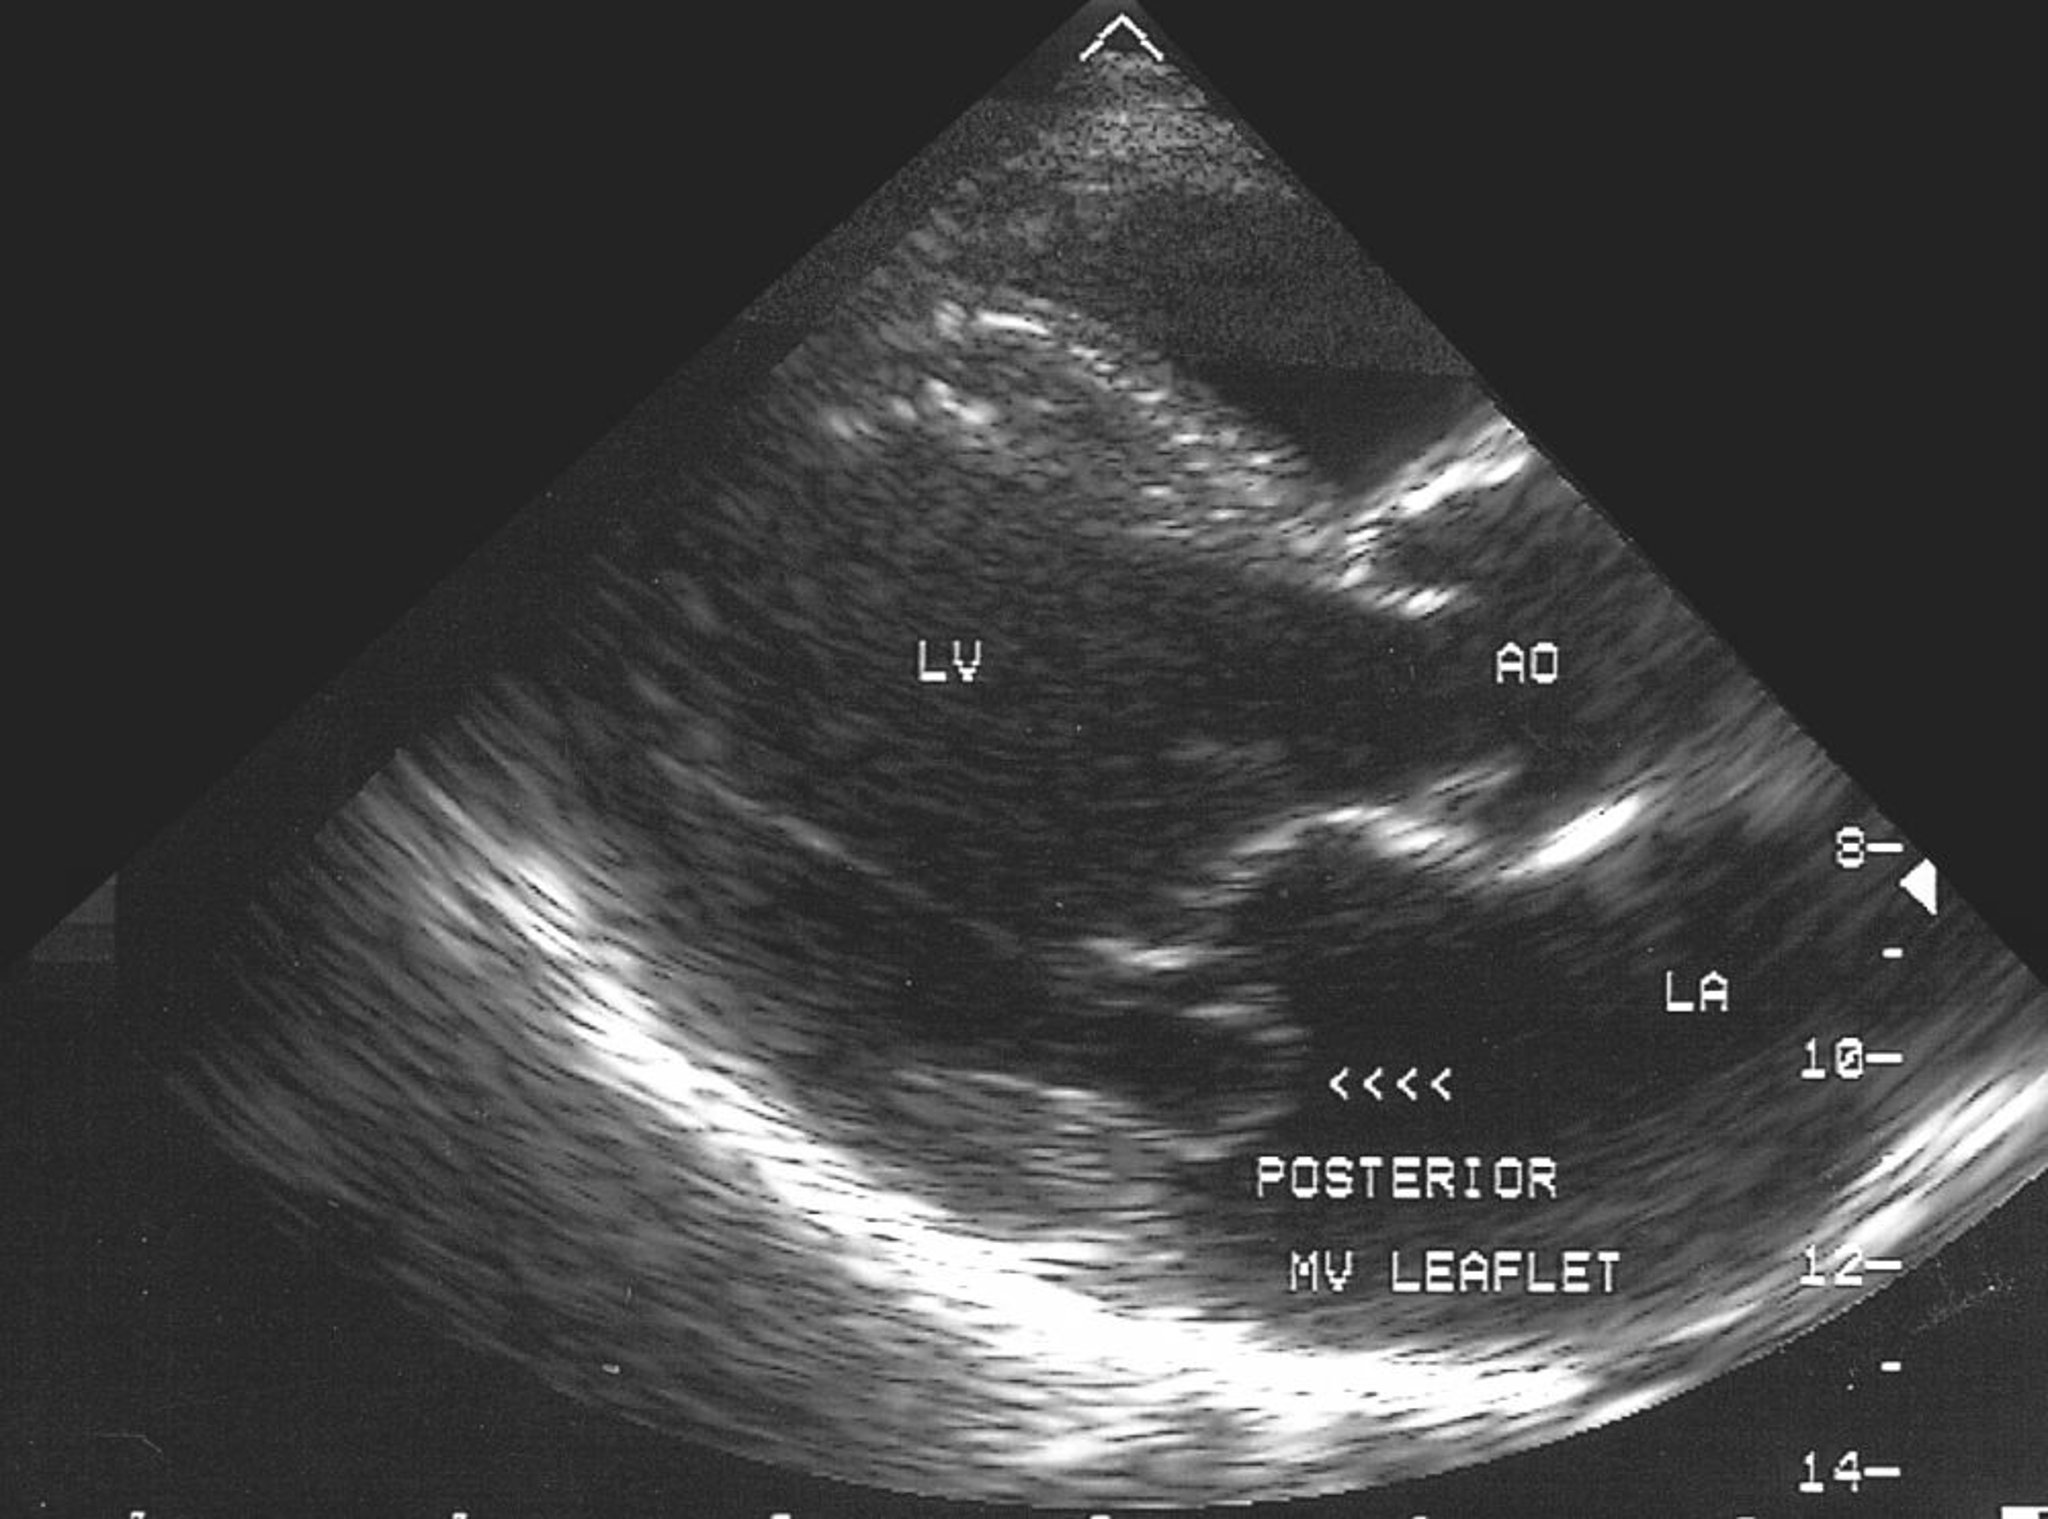

Mitralklappenprolaps (Echokardiogramm)

Diese echokardiographische Aufnahme zeigt einen Prolaps des hinteren Segels der Mitralklappe in das linke Atrium (LA).